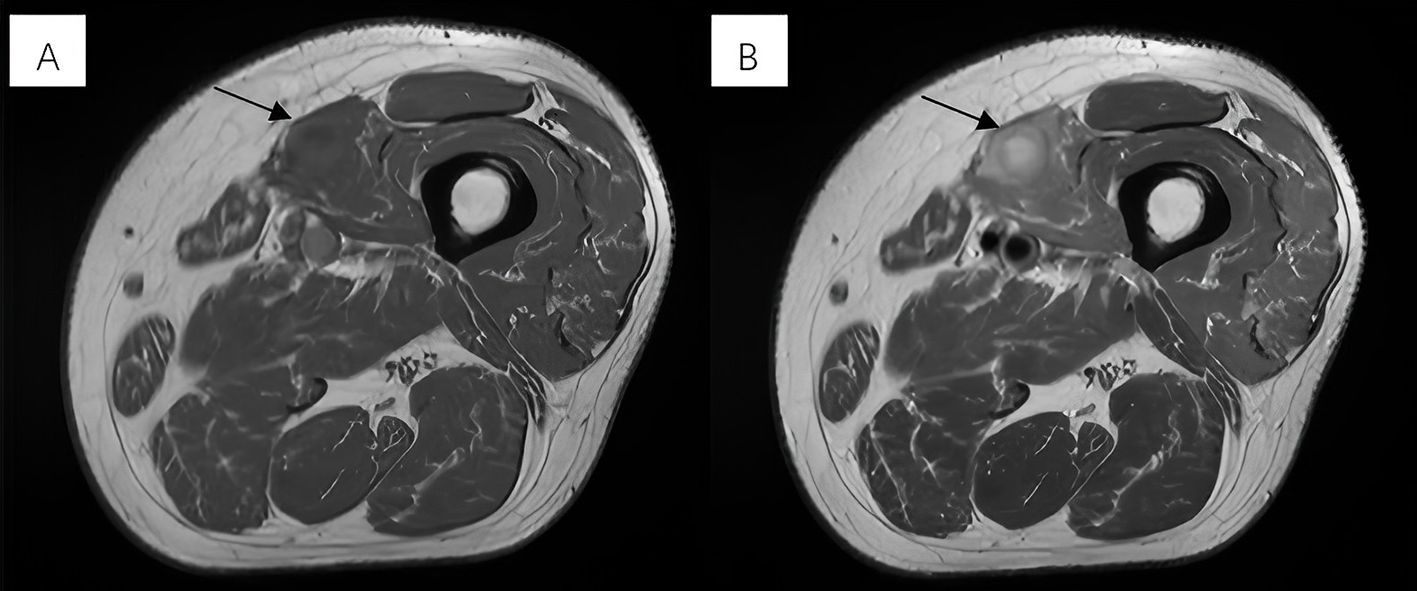

For more evaluation, MRI revealed a near-oval lesion within the vastus medialis muscle with the largest diameter measuring approximately 25 mm. Exhibiting iso-intensity on T1-weighted images and mixed hyperintensity on T2-weighted images (Figures 1A, B). The lesion demonstrated significant hyperintensity on diffusion-weighted imaging (DWI). The MRI report suggested a tumor-like lesion within the left vastus medialis muscle, surgical intervention is recommended.

Figure 1. (A) Exhibiting iso-intensity on T1-weighted images. (B) Mixed hyperintensity on T2-weighted images.